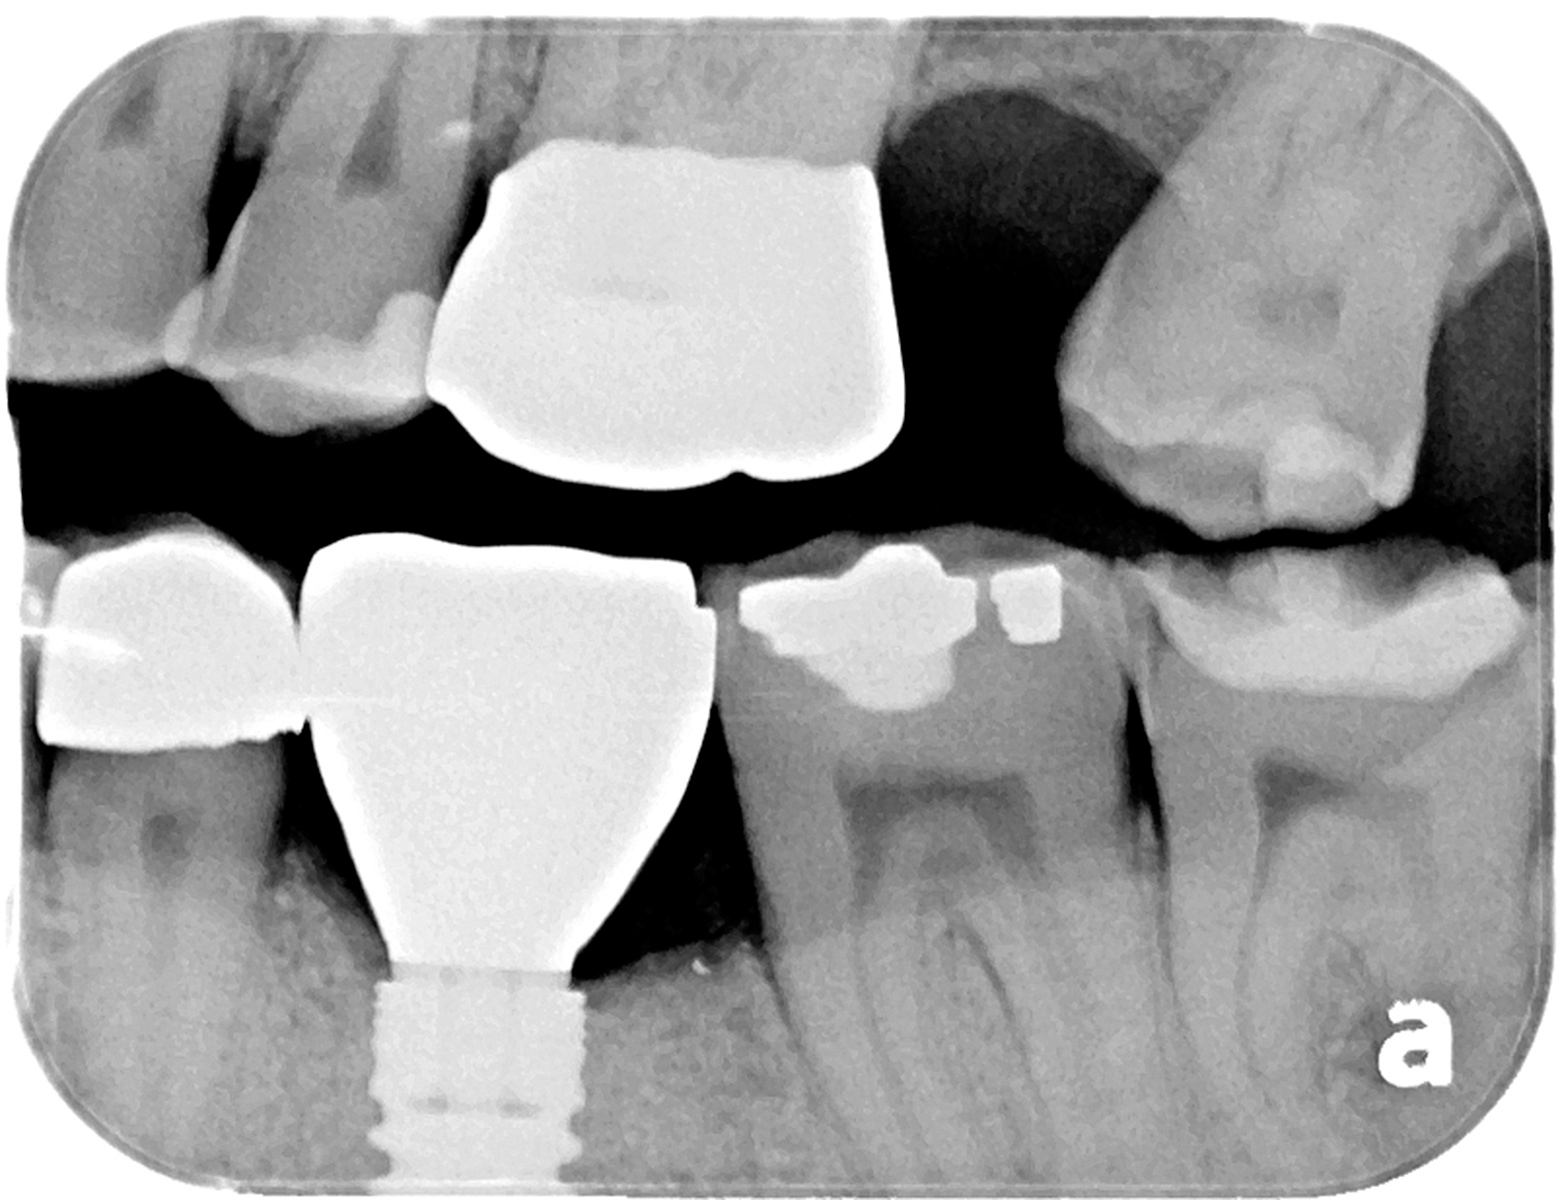

(A) Ceramic crown cementation. (B) Final radiograph. Download

(A) Ceramic crown cementation. (B) Final radiograph. Download Ceramic Porcelain Crown Radiograph Radiographs aid in clinically determining crown fit, specifically interproximal. in the clinical evaluation, anatomical form (p = 0.009) and occlusion (p = 0.001) showed significant differences. radiographs aid in clinically determining crown fit, specifically interproximal margins where tactile and. Statistical analysis was performed to determine whether each crown type was correctly evaluated for acceptable or unacceptable marginal fit.. Ceramic Porcelain Crown Radiograph.